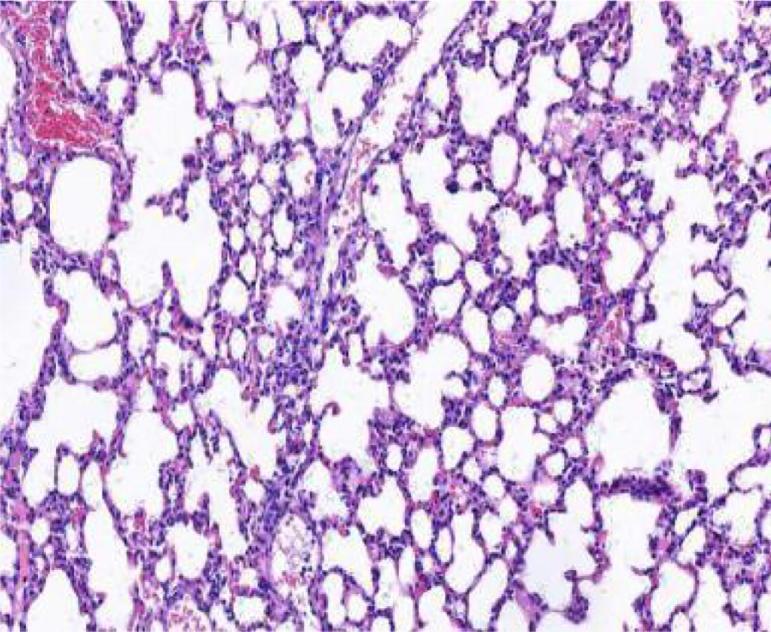

Compared with model group, the Schisandrae Fructus syrup groups can significantly increase the tidal volume of mice and decrease the respiratory frequency and the degree of bronchial stenosis ( < 0.01); The Schisandrae Fructus syrup groups can decrease the levels of NO and IL-6 in serum and improve the pathological changes of lung and bronchus in different degrees.

与模型组相比,五味子糖浆组可显著增加小鼠潮气量,降低呼吸频率及支气管狭窄程度(P<0.01);五味子糖浆组可降低血清中NO和IL-6水平,不同程度改善肺及支气管的病理变化。